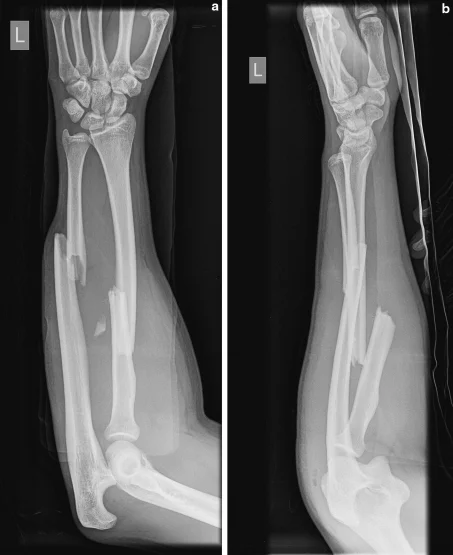

- x-ray AP and lateral view of forearm, show a displaced fracture in both radius and ulnar shaft with elbow dislocation

Site â midâshaft forearm

Fracture type â simple radius & ulna

Fracture line â transverse across both bones

Displacement â 90° rotation of radius & ulna

Imaging â one joint captured in an AP view, the other in a lateral view on the same film

Special considerations â accurate anatomical reduction and absolute stability (a joint) are essential; note that TheddyâSlongo principles may not apply to forearm fractures.

Site: midâshaft forearm

Type: simple radius / simple ulna fracture

Fracture line: transverse across both radius and ulna

Displacements:

- 90° rotation of both bones

- 35° posterior tilt of both bones

Special issues:

- Requires accurate anatomical reduction and absolute stability (a joint)

Note: The Slongo technique may not apply to forearm fractures; always verify fracture lines.